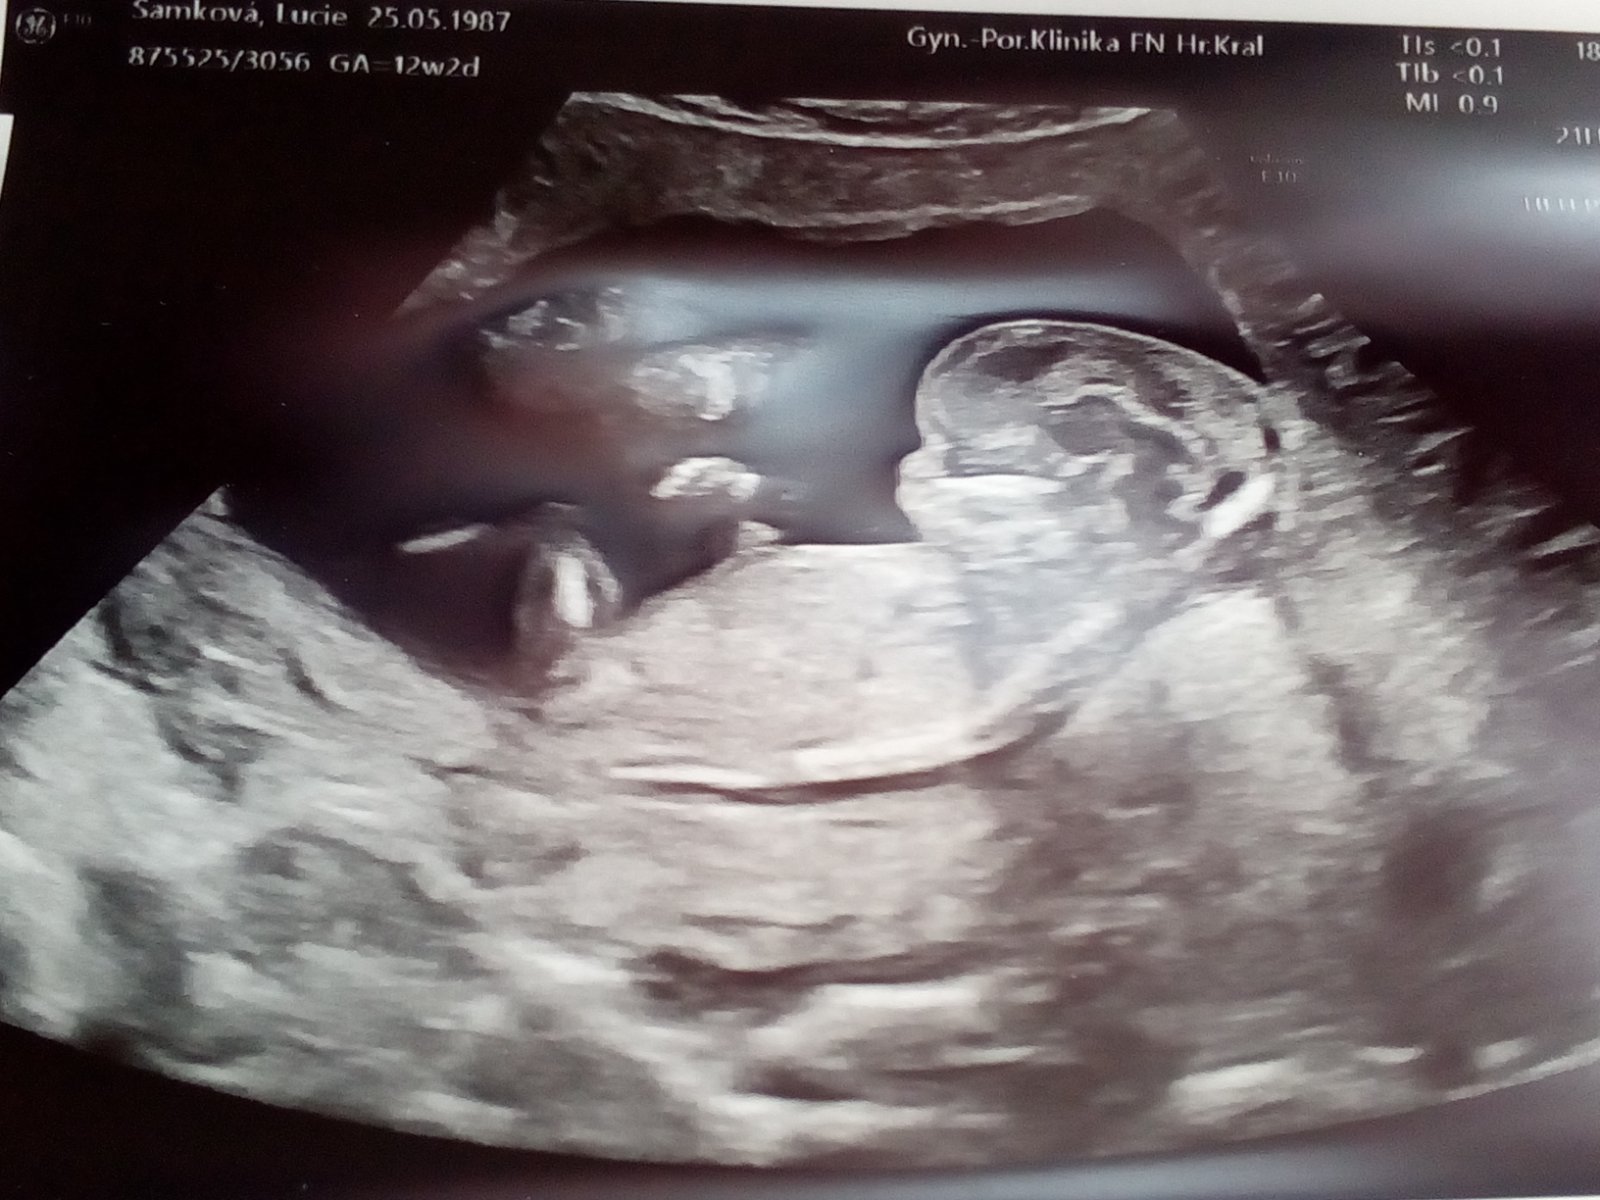

Prosím našel by se tu někdo kdo by na 100%poznal pohlaví miminka děkuji

Holka nebo kluk. Pozná tady někdo na 100 %?

@patrollla na 99% asi jen doktorka.

Na 100% to budete vědět za pouhých cca 188 dni 😉 ale typla bych holku

Takhle se to nedá poznat. Určuje se to z pohledu mezi nozmičkami, takhle to nepozná nikdo 🙂

A 100% je až porod 🤓

Jestli to nepoznal lékař, tak tady to tuplem nikdo nepozna 🤷‍♀️